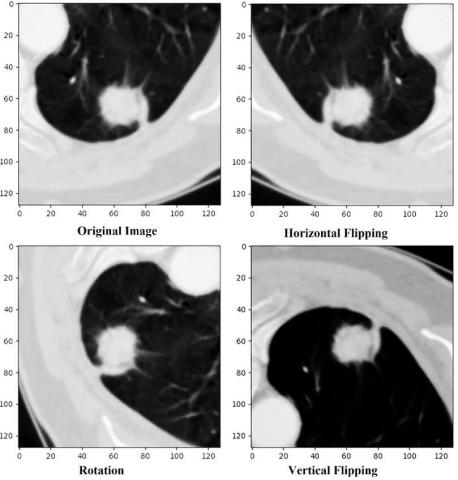

After preprocessing, data augmentation is performed to increase the data size and evaluate the effectiveness of the model with and without data augmentation. A total of three augmentation techniques were implemented, extending each data sample to 4 samples, resulting in a total of 62,200 samples. The three techniques for geometric transformation invariance, including horizontal flipping, vertical flipping, and rotation, are defined below and illustrated in Figure 3.

Figure 3. Original image and three augmented variations

3.3.1 Horizontal and vertical flipping

These techniques are used to simulate changes in lung nodule orientation. Nodules can appear on either side or in multiple positions within the lungs, and flipping helps the model recognize consistent features regardless of orientation.

3.3.2 Rotation

It is designed to correct slight positional shifts that may occur during medical scans due to patient posture. By introducing rotations, the model becomes more adaptable to these positional variations, thereby enhancing its segmentation accuracy across different nodule locations.